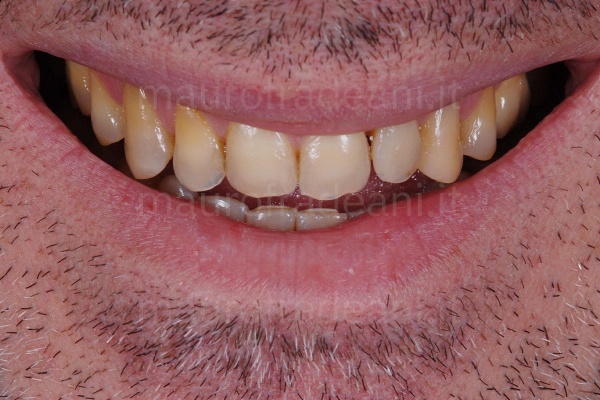

1/6: Dental abrasion and shortening heavily penalize the young patient's smile.

2/6: With lips parted, no dental portion is exposed, due to reduced tooth lengths. Since this is a peculiar characteristic of elderly patients, the resulting esthetic deficit is particularly evident due to the young age.